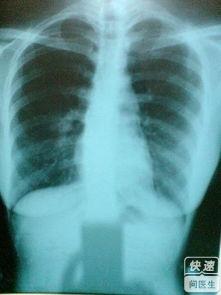

3、根据胸痛的特征,常可作出胸膜炎的诊断。医生使用听诊器可闻及一种吱吱的摩擦音,称为胸膜摩擦音。尽管胸部X线检查不能显示胸膜炎,但可发现肋骨骨折、肺部病灶或少量胸腔积液。